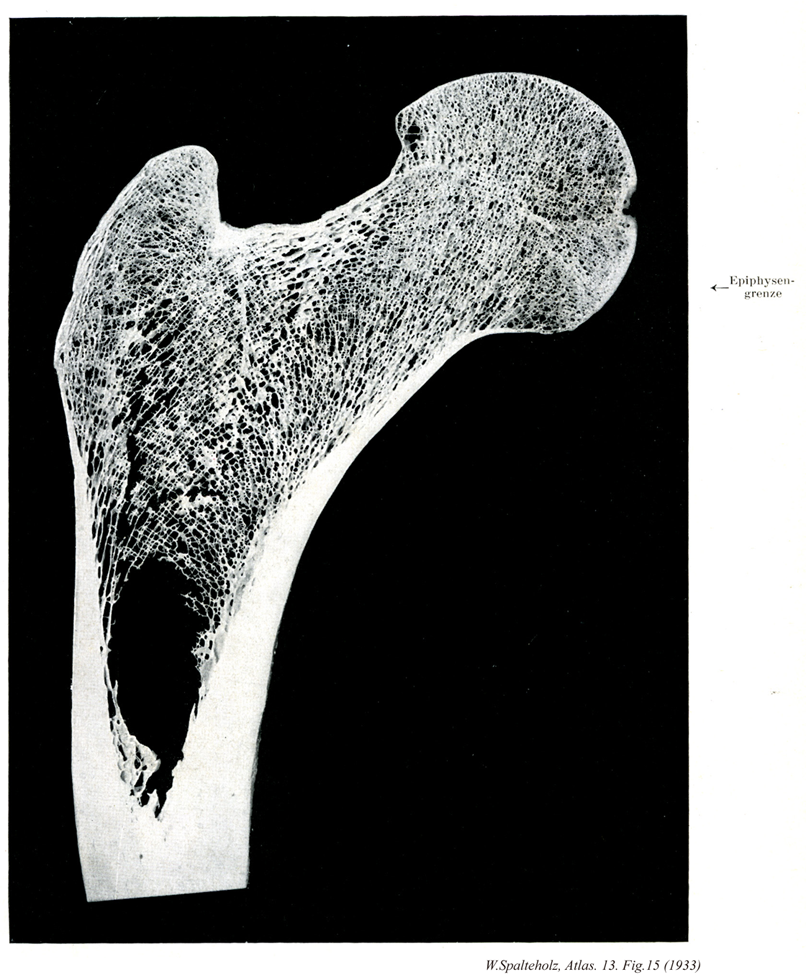

015